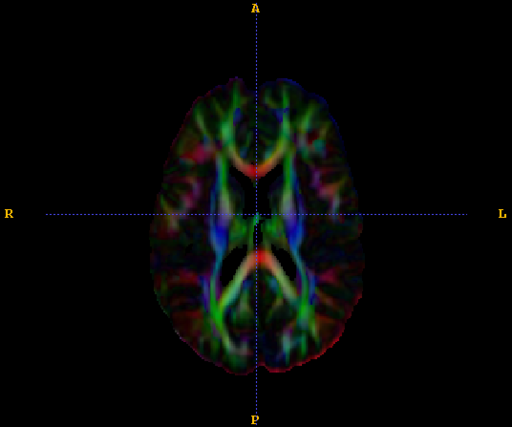

• We implement the diffusion weighted image (DWI) registration model from the paper of G.K.Rohde etl. Patient head motion and eddy currents distortion cause artifacts in maps of diffusion parameters computer from DWI. This model corrects these two distortions at the same time including brightness correction.

Coronal slice from a unregisted DTI (left). The same slice after applying the registration model (right).